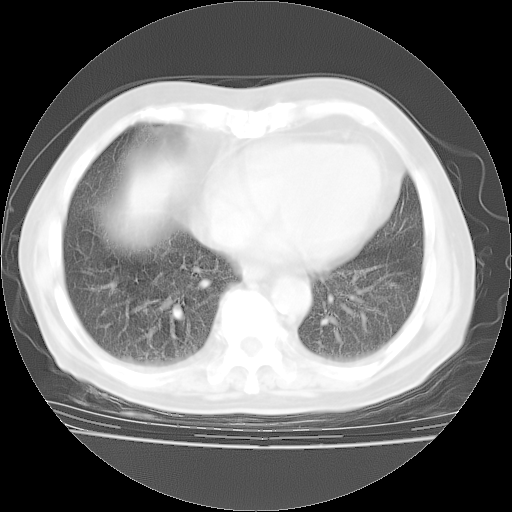

4月28日肺部CT——再次出现类似去年5月9日——透光度降低,“间质性”改变。

4月28日肺部CT——再次出现类似去年5月9日——磨玻璃样、间有“粟粒样”改变。

个人阅读4.14日肺部CT平扫:纵隔窗无异常,但肺窗示:双下肺内、后基底段有片絮状侵润影,部位以后基底段为著,以间质改变为主,呈急性肺泡炎征像,和首次住院影像学有相似之处。仅是个人读片,明日请相关专家再读片哈。其它建议同上。